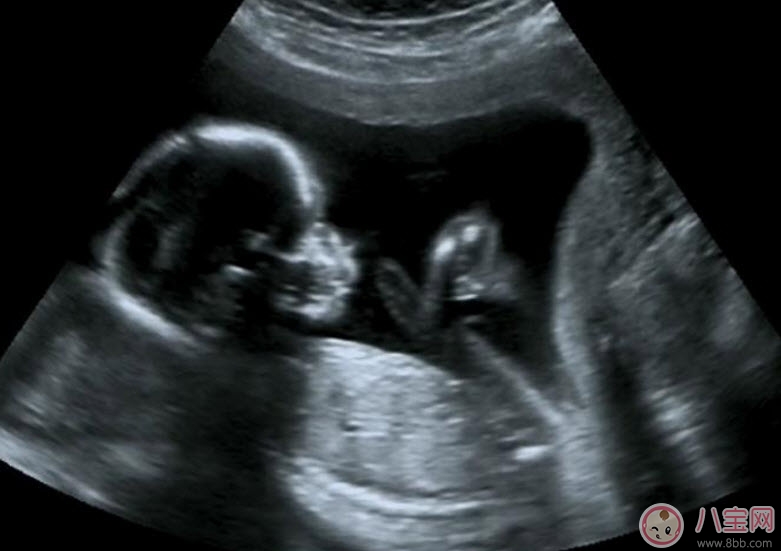

2、了解胎兒生長發育情況

B超既可以測量胎兒的各個部位,如胎頭大小、胎臀長度,也可以用于在早期妊娠來測定胎兒的具體懷孕時間(醫學上叫做孕周),測定胎頭的雙頂徑、頭圍、腹圍及胎兒股骨的長度等,這些數據可以判斷胎兒的生長發育情況。

5、觀察胎兒生理活動情況

B超能夠直觀胎兒在母體內的活動狀況,諸如呼吸情況、胎兒的運動、整個身體大的運動、肢體的運動、胎兒的吞咽動作等等,可以一覽無余。之外,通過觀察胎兒的張力是否良好,可以判斷胎兒在宮內是否缺氧或者受到損害,準確預報胎兒安危。